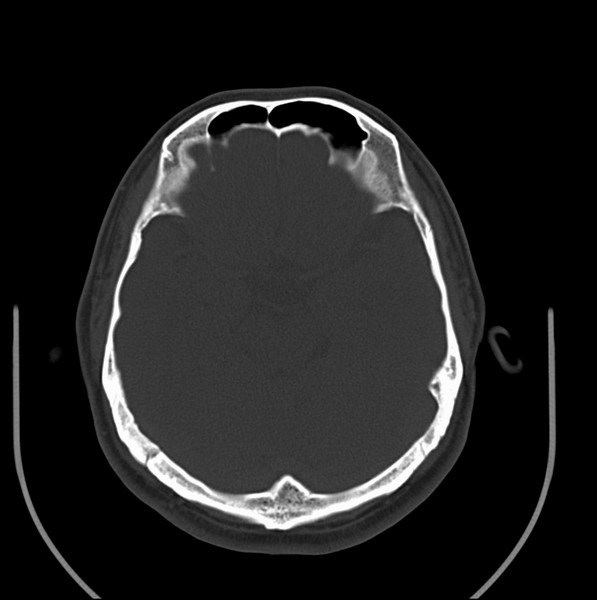

男、30、发现鼻咽部肿瘤侵犯海绵窦,未发现明显淋巴肿。请问国内那家医院治疗鼻咽部肿瘤最好?手术以何种方式为主?病灶可否全部切除?急切期待的大家的帮助。

扫描示鼻咽腔不对称,中度狭窄,右侧咽隐窝消失,局部软组织肿块,鼻咽右侧壁增厚形成肿块,突入鼻咽腔,肿块平扫呈等密度,肿块向深部侵润,右侧翼内外肌受侵,右侧咽旁间隙变窄;向后生长,头长肌界线欠清,向后上生长侵犯同侧颈动脉鞘区。双侧海绵窦增宽,内见软组织影与鼻咽部肿块相连。考虑鼻咽癌。鼻咽癌主要是放射治疗,且效果较好;到当地有治疗设备较大医院治疗即可。

这个病例有点特殊,和常见的鼻咽癌不太一样,以向颅内侵犯为主,骨质破坏区小。鼻咽癌首先要考虑,有没有其他可能?本人不会看mr片,期待有人能讲解,期待病理。